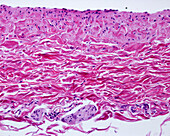

13416586 - Aorta tunica media and adventitia, light micrograph

12634941 - Aorta, tunica adventitia and media, LM

12634940 - Aorta, tunica adventitia and media, LM

12634939 - Aorta, tunica adventitia and media, LM